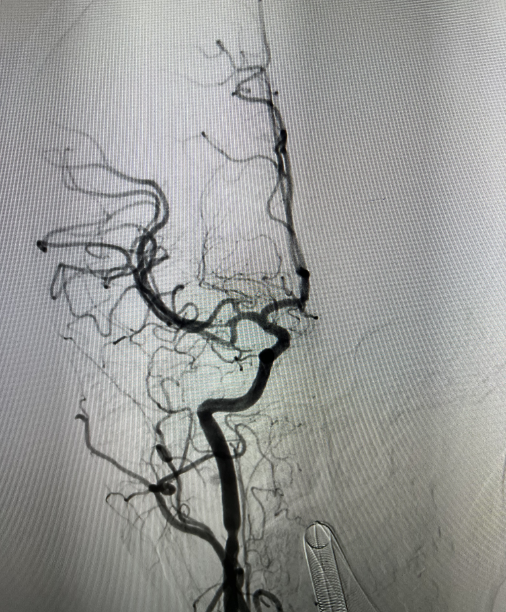

术后检查